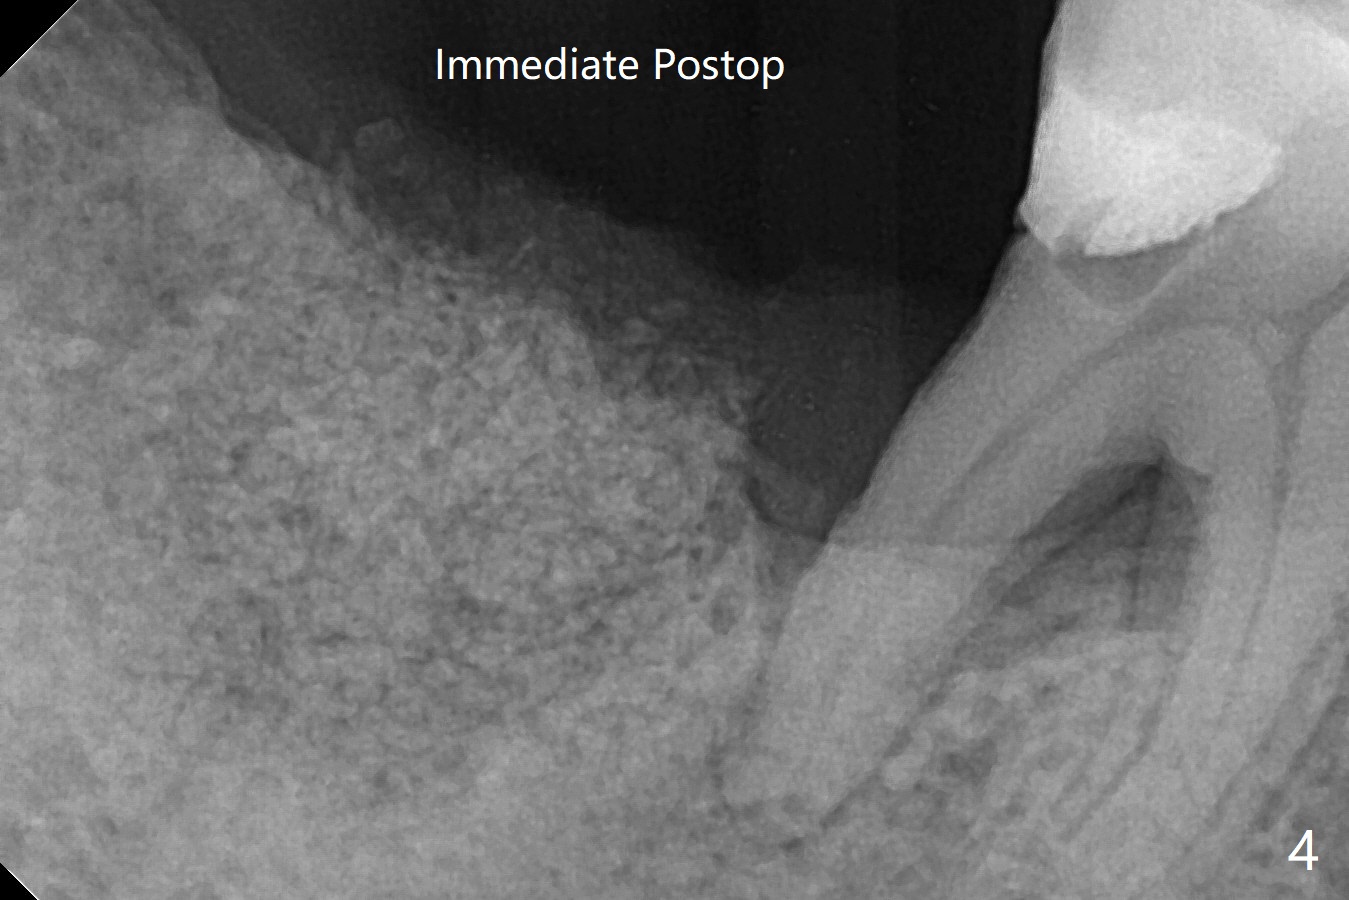

After extraction of the tooth #31 with mesial root fracture and a buccal fistula (Fig.1 <) and debride-ment, cortical: cancellous (50: 50) mineralized allograft (.5-1 mm) saturated with ~ .3 ml of .3 mg/ml of rhPDGF-BB (one component of GEM21S) is placed in the socket. Amazingly bone graft granules seem to stick to each other (semi sticky bone (Fig.2), as compared to PRF). The socket opening is covered with a piece of Osteogen plug and 12x12 mm Amnion-Chorion Allograft, followed by 4-0 PGA suture (Fig.3). The bone graft is packed as apical (Fig.4) and buccal (Fig.5 B) as possible. The patient will return to soft tissue healing check in a week. CT will be taken to determine whether the buccal plate is repaired 4 months postop. Watch Video. In fact COVIT 19 delays her return. The buccal plate seems to have reformed 7 months postop (Fig.6 >). The width and height of the ridge remains basically the same (compare Fig.7 and 8).